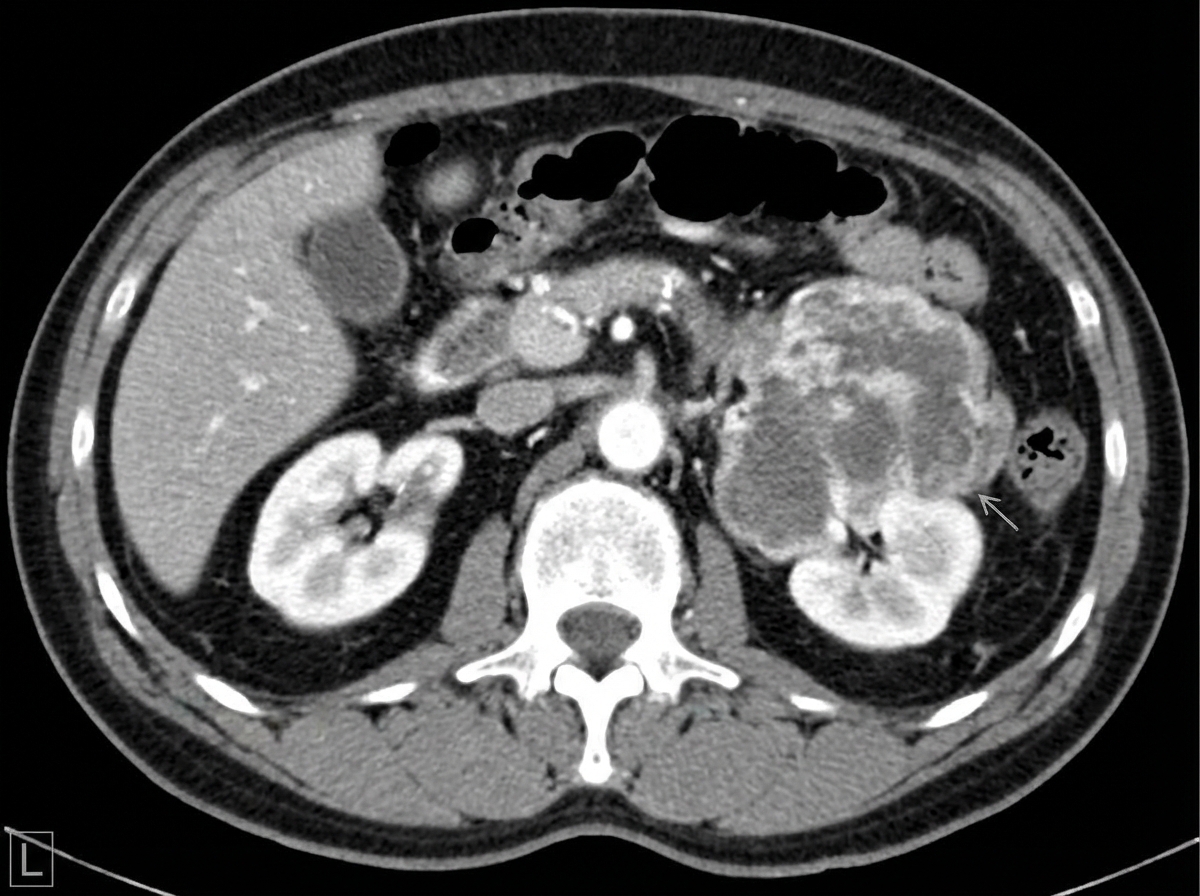

A 74-year-old male presents to his primary care physician complaining of left lower back pain. He reports a four-month history of worsening left flank pain. More recently, he has started to notice that his urine appears brown. His past medical history is notable for gout, hypertension, hyperlipidemia, and myocardial infarction status-post stent placement. He has a 45 pack-year smoking history and drinks 2-3 alcoholic beverages per day. His temperature is 100.9°F (38.3°C), blood pressure is 145/80 mmHg, pulse is 105/min, and respirations are 20/min. Physical examination is notable for left costovertebral angle tenderness. A CT of this patient’s abdomen is shown in figure A. This lesion most likely arose from which of the following cells?